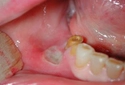

4. İnflamatuar HastalıklarBazı inflamatuar hastalıklar, dil ve damak uyuşmasına neden olabilir. Örneğin, ağızda meydana gelen aftlar veya lökoplaki gibi durumlar, dilin hissini etkileyebilir. Ayrıca, romatoid artrit gibi sistemik inflamatuar hastalıklar da sinirlerin etkilenmesine yol açabilir.